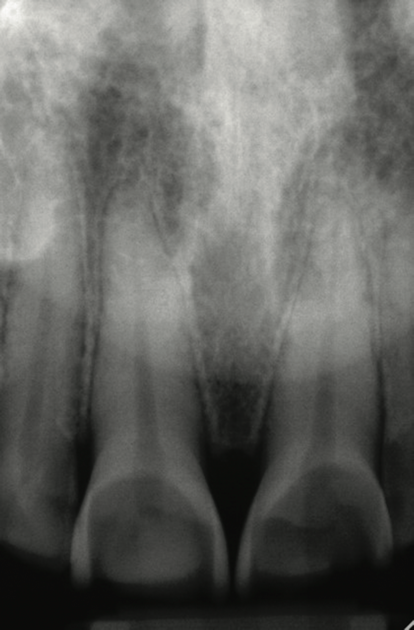

Another intrinsic factor is the patient's gastric acid entering the oral cavity. The source of intrinsic stomach acid may range from rumination or gastroesophageal reflux to chronic alcoholism, pregnancy, or vomiting caused by anorexia nervosa or bulimia nervosa.13 Figure 1 through Figure 3 show the radiographic presentation and clinical examples of dental erosion in advanced stages in the same patient caused by the combination of bulimia nervosa and chronic alcoholism.

Fig 1. Radiographic image of maxillary incisors presenting signicant radiolucency representative of enamel and dentin loss.

Figure 1